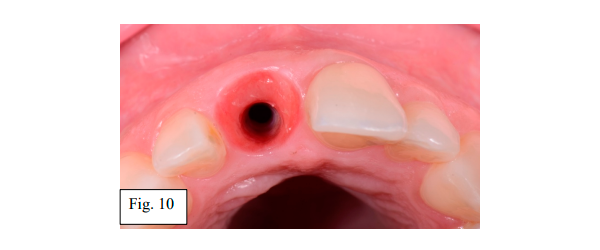

Após um período de três meses para maturação e organização do tecido peri-implantar, iniciou-se procedimentos protéticos para a confecção da coroa utilizando fluxo digital (Dr. Álvaro Martins / TPD. Paulo Caixeta – Laboratório 3D). A coroa provisória foi retirada e a osseointegração foi confirmada clinicamente (Fig. 10).